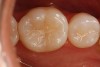

Another preparation technique is the use of air abrasion to remove the area of decay. Figure 1 shows tooth No. 19 with a sealant restoration. Using the Diagnodent, recurrent decay was detected. An air abrasion system was used to remove the old sealant restoration as well as the recurrent decay without the need for local anesthetic (Figure 2). The use of air abrasion allows for the efficient removal of the old resin material as well as the removal of the carious tooth structure.

Figure 1  An old sealant restoration with recurrent decay present.

Figure 1